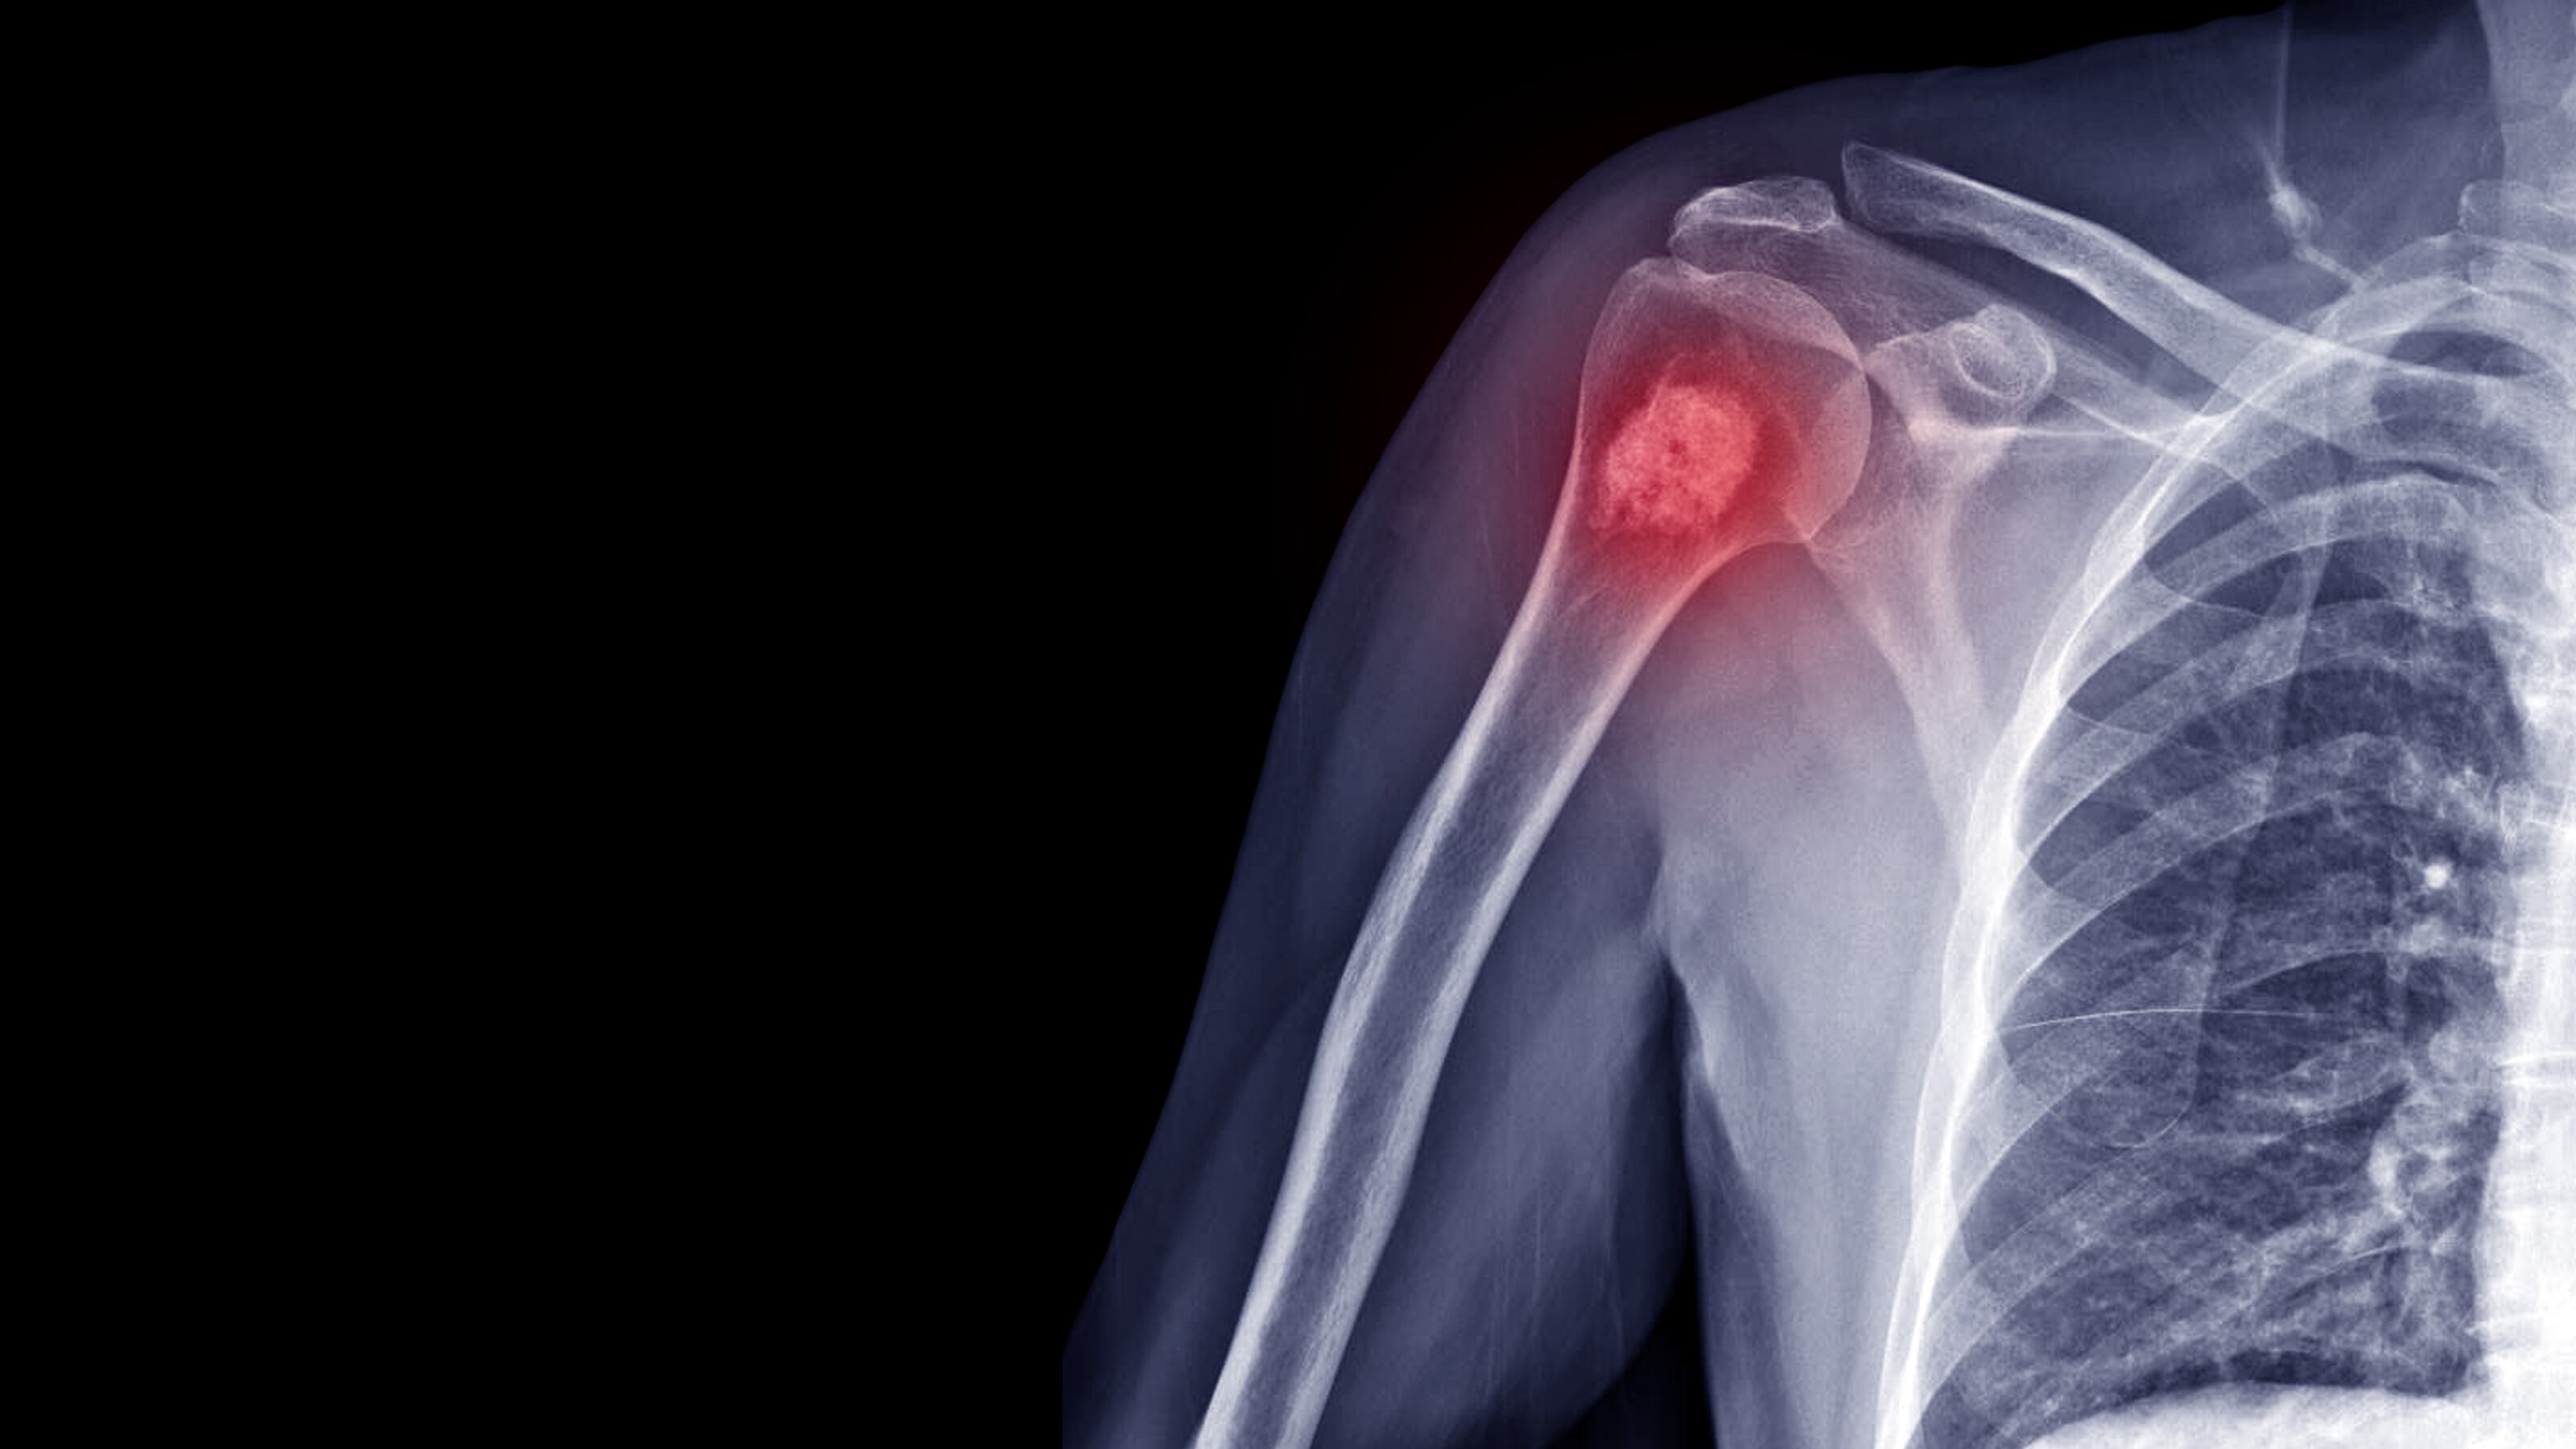

Rayos X del hueso del hombro derecho.

El cáncer en los huesos es una enfermedad compleja que se origina en las células óseas. Foto: Getty Images

Entre los tipos de cáncer óseo primario más comunes se encuentran el osteosarcoma, el condrosarcoma y el sarcoma de Ewing. Según la Sociedad Americana del Cáncer, el osteosarcoma suele aparecer en los huesos largos, como los del brazo y la pierna, y es más frecuente en adolescentes y adultos jóvenes. El condrosarcoma se origina en el cartílago, mientras que el sarcoma de Ewing afecta a los huesos y tejidos blandos cercanos, siendo más frecuente en niños y adolescentes.

El cáncer en los huesos es una enfermedad compleja que se origina en las células óseas. Este tipo de cáncer puede ser primario, cuando se inicia directamente en el tejido óseo, o secundario, cuando es una extensión de cáncer de otro órgano. Según el Instituto Nacional del Cáncer (NCI) de los Estados Unidos, los tumores óseos primarios son relativamente raros en comparación con otros tipos de cáncer, siendo más comunes en personas jóvenes.